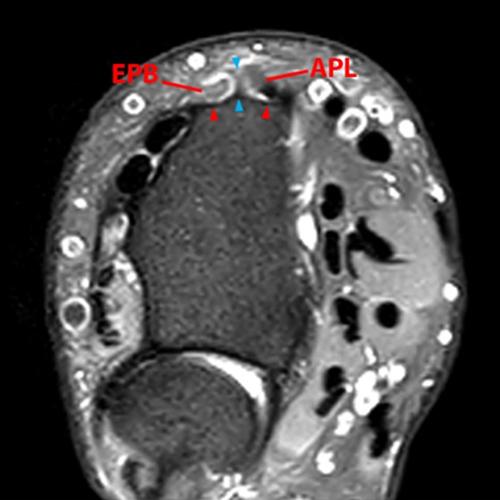

Clinical History: A 68-year-old female presents with radial-sided pain and swelling. Axial T1-weighted (1A), axial fat-suppressed proton density-weighted (1B), and coronal fat-suppressed proton density-weighted (1C) images are provided. What are the findings? What is your diagnosis?

Figure 2: The axial T1-weighted (2A), axial fat-suppressed proton density-weighted (2B), and coronal fat-suppressed proton density-weighted (2C) images demonstrate a thickened extensor retinaculum, surrounding soft tissue edema, and fluid signal in the first extensor compartment of the wrist (arrowheads). Marrow edema is noted within the subjacent radius (asterisks). A single extensor pollicis brevis and two abductor pollicis longus tendon slips are present with heterogeneous intrinsic signal.